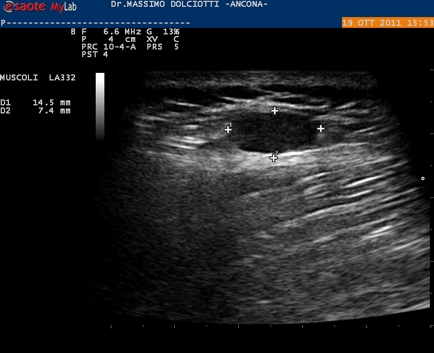

Ecografia del: 19/10/2011

Strumento: Esaote MyLab 50 Gold - Responsabile Linea Cardio Esaote Regione Marche Dr. Franco Fabi

Sonda: Lineare Multifrequenza 5-10 MHz

Età Paziente: M 42 anni

Motivazione dell'esame: tumefazione mobile, lievemente dolente alla pressione in sede dorso lombare sinistra presente da circa 2 anni.

Conclusioni: lesione solida benigna per i criteri ecografici.